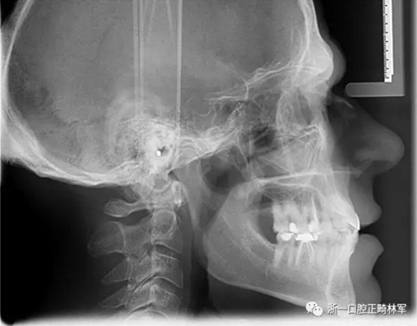

一位尋求改善微笑面容的43歲荷蘭阿爾梅勒男子通過其全科牙醫(yī)的介紹來到一家正畸醫(yī)生的私人診所,以糾正其錯合畸形并在上頜前牙區(qū)域放置6個貼面。他屬于牙形I類錯合畸形,輕度骨性III類,覆合和覆蓋減少以及前牙區(qū)存在間隙(圖1)。

在最初的正畸咨詢期間,拍攝了口內(nèi)和口外照片連同一張全景片(圖2),一張側(cè)位頭影片(圖3)和正畸研究模型的海藻酸鹽印模。